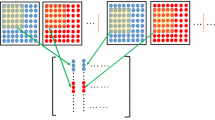

Parallel magnetic resonance imaging (MRI) is an imaging technique by acquiring a reduced amount of data in Fourier domain with multiple receiver coils. To recover the underlying imaging object, one often needs the explicit knowledge of coil sensitivity maps, or some additional fully acquired data blocks called the auto-calibration signals (ACS). In this paper, we show that by exploiting the between-frame redundancy of dynamic parallel MRI data, it is possible to achieve simultaneous coil sensitivity map estimation and image sequence reconstruction. Specially, we introduce a novel two-stage approach for dynamic parallel MRI reconstruction without pre-calibrating the coil sensitivity maps nor additionally acquiring any fully sampled ACS. Numerical experiments demonstrate that, the performance of the proposed approach is better than other state-of-the-art approaches for calibrationless dynamic parallel MRI reconstruction.